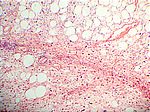

Liposarkom, HE